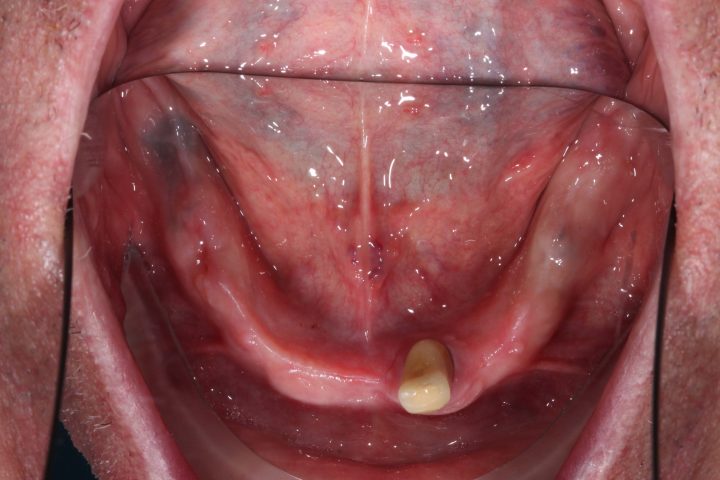

PRIMA

dopo

Arcata superiore - Fase iniziale, intermedia e finale

Caso risolto con Toronto Bridge - Fase iniziale, intermedia e finale